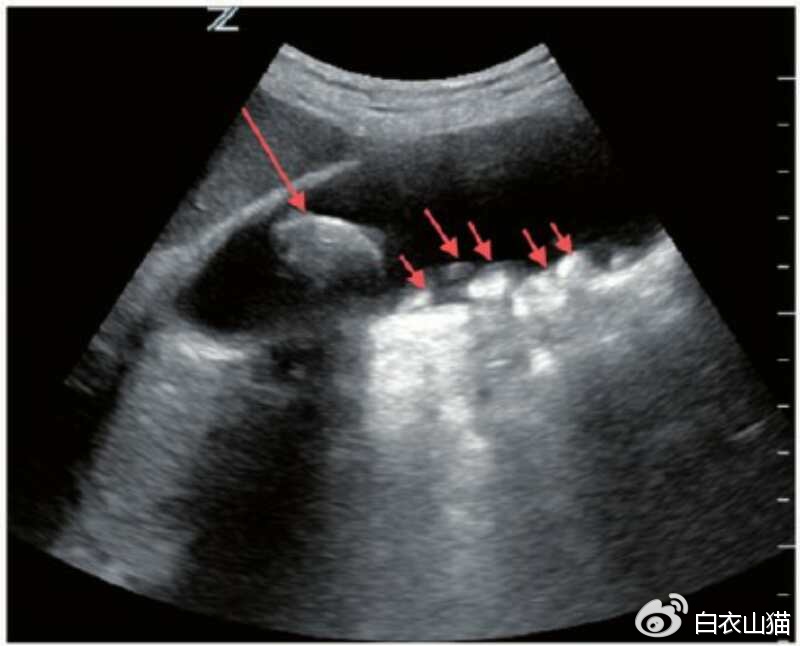

B超怎么来判断息肉和结石呢?

结石的B超表现有:胆囊腔强回声、后 方伴会有声影、声像具体表现会随着患者体位的改变 而发生移动现象。

红箭头指向结石。

部分结石,比如胆固醇结石,比较疏松的时候,可以没有声影。这个时候,恰好结石又粘附在胆囊壁上,当然不会随体位变化而移动啦。这部分结石,会被B超下判断为息肉。